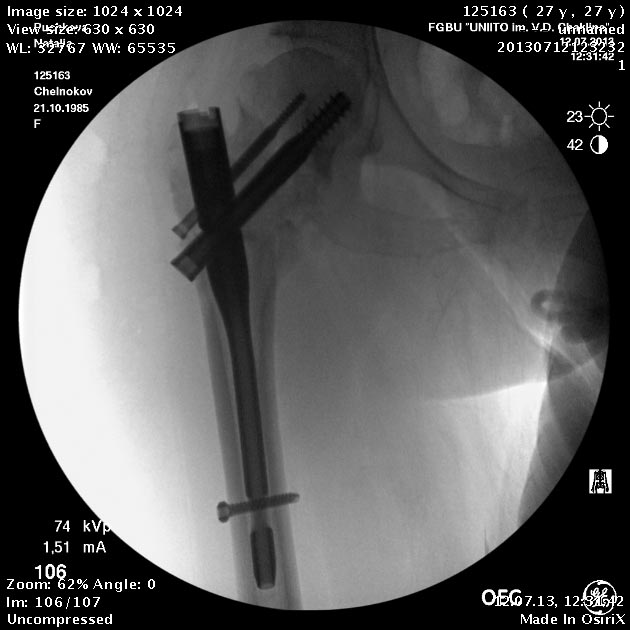

Пациентка приехала на этой неделе. Сегодня сделали правое бедро. Удалили

винты, сделали чрескожную вальгизирующую остеотомию, зафиксировали

Affixus. Второе бедро будем делать недели через 2.